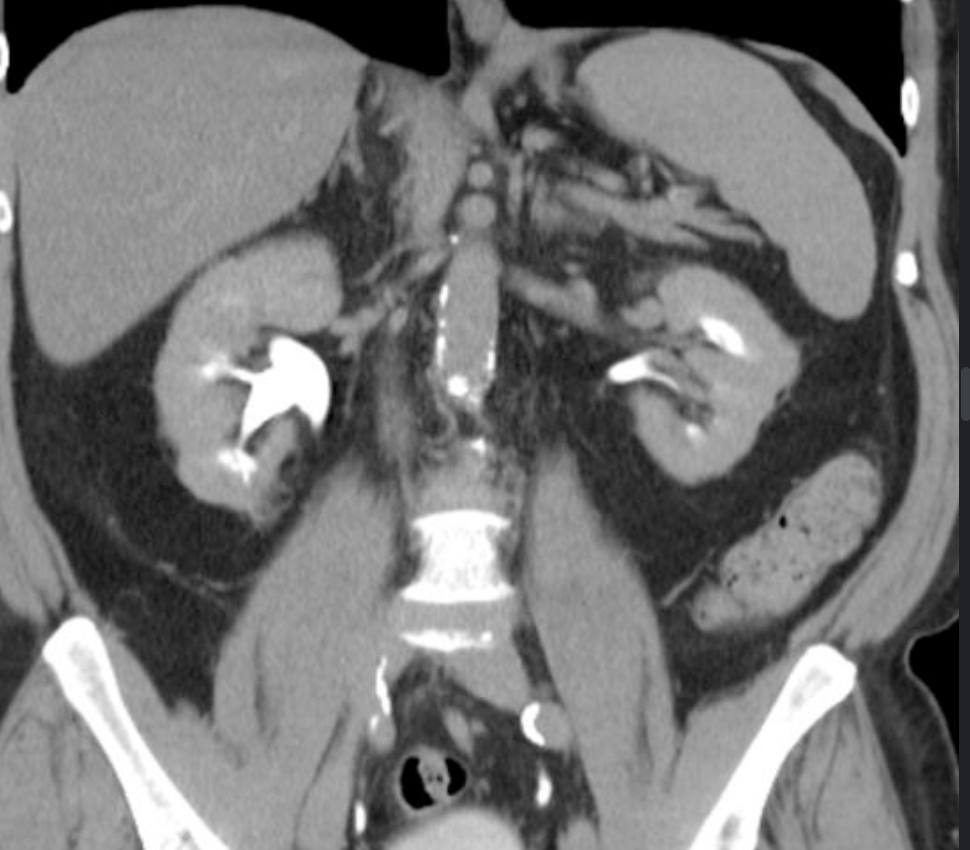

Acquired Cystic Renal Disease

• 3+ cysts per kidney in patient with CKD

• Typically in long term dialysis patients

• Mildly increased risk of RCC - however the RCC that occurs tends to be less aggressive